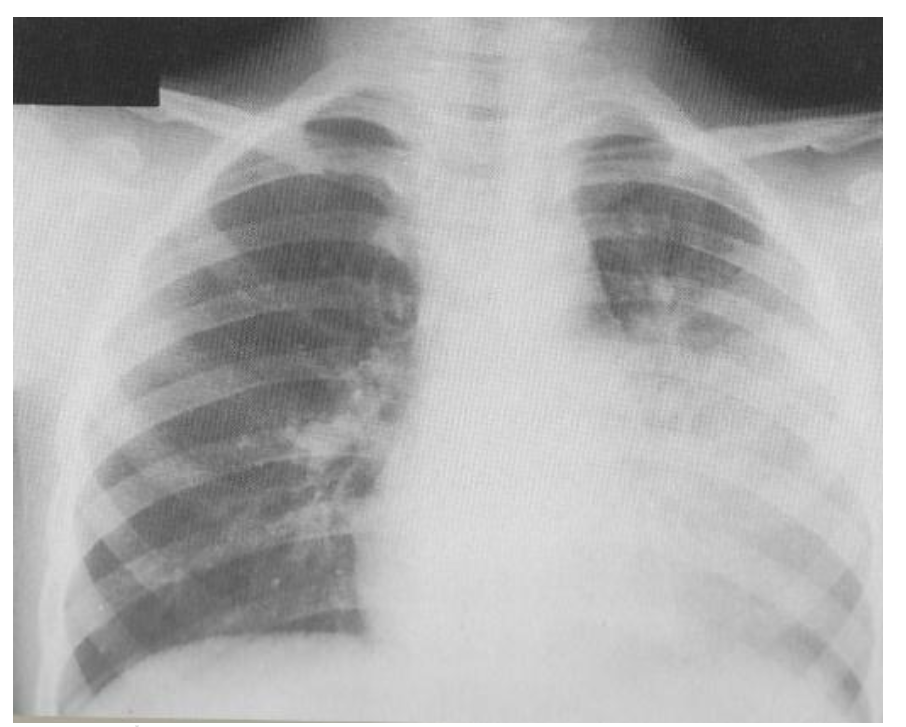

このような場合、より深刻であると考えられる場合、医療専門家は、肺炎または無気肺(肺の部分的または完全な虚脱)の兆候を確認するためにを要求することがあります。この検査では、この器官が過膨張しているかどうか(空気で満たされているかどうか)、または横隔膜が低いかどうかもわかります。これは、子供が呼吸しようと非常に努力していることを示しています。